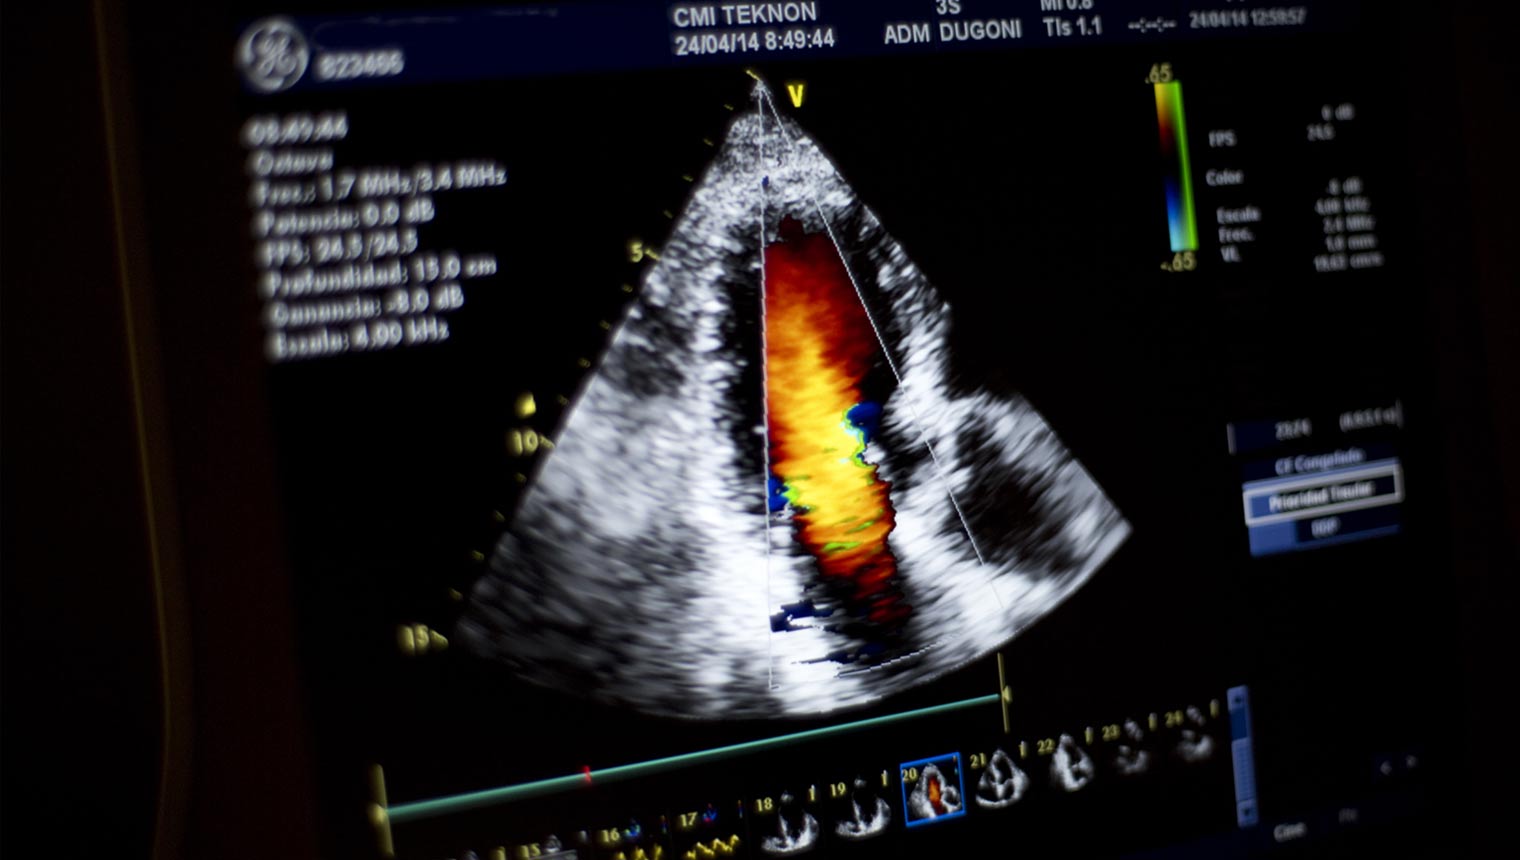

In some treatments, such as oncology or cardiovascular diseases, a periodic check-up can be the tool to follow the evolution and remission of the disease.

Hospital Quirón Teknon has quality professionals in all medical-surgical specialties, supported by the latest in infrastructure and technology. Thus, we are prepared to offer you, in only one day, a complete, comprehensive and personalized diagnosis, with an adaptable circuit that facilitates further testing as would be the need as ordered by the coordinating specialist of the check-up. We guarantee maximum personalization of the check-up through five program types (five program types (Comprehensive Check-up, Oncology Check-up, Cardiovascular Check-up, Sports Check-up, Dental Check-up).